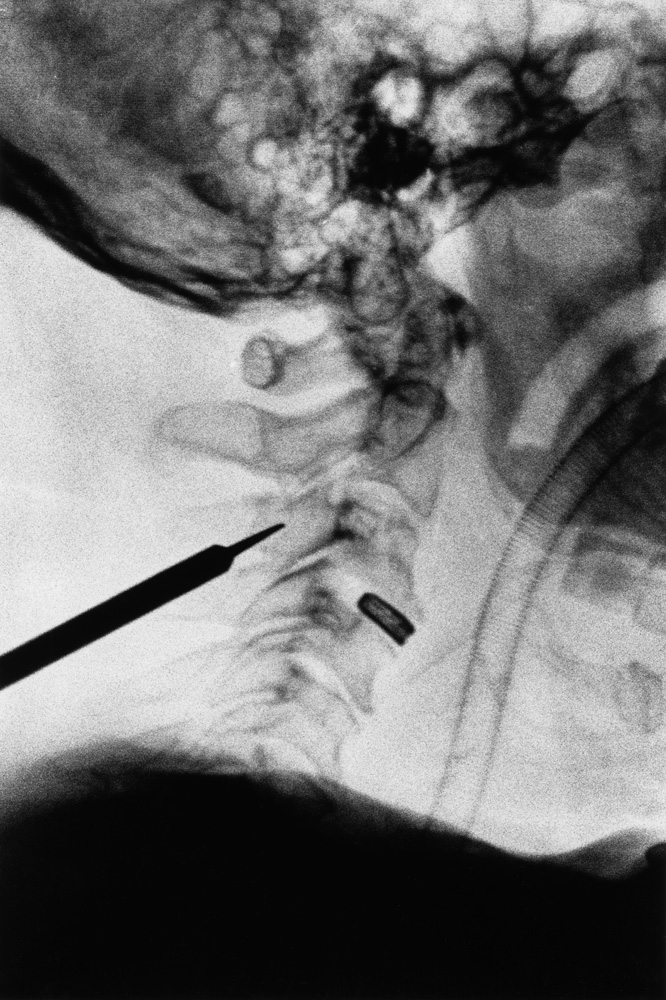

Da metà giugno a fine novembre 2021, Renato D’Agostin e la sua macchina fotografica hanno avuto accesso esclusivo alla clinica: dal centro di riabilitazione alle sale operatorie, dai reparti di degenza all’area amministrativa, dal laboratorio di analisi agli ambulatori.

Il risultato di questo viaggio immersivo nel mondo e negli spazi della struttura sono oggi 20 scatti unici e irripetibili, raccolti in questo catalogo e nella mostra “La Cura.

La clinica Rizzola nelle fotografie di Renato D’Agostin” ospitata presso Spazio Mostre Italvanto Battistella, a San Donà di Piave, dal 7 al 17 gennaio 2022 Gli scatti trovano oggi esposizione permanente all’interno della Casa di Cura Sileno e Anna Rizzola.